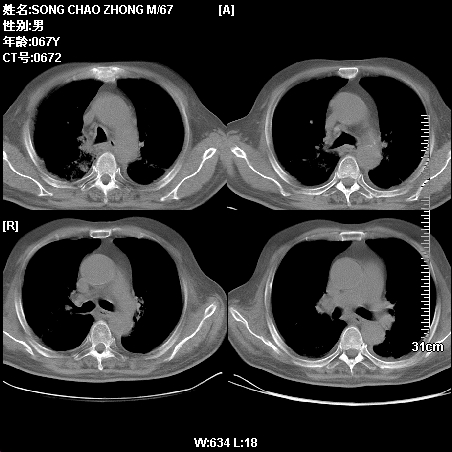

肿瘤科住院病人,都有食管癌史,都有放化疗治疗,两下肺病变是转移灶?还是其他原因造成?请老师指点

病例二 食管癌4个月,咳嗽咳痰,呼吸困难

第一个病例我感觉不是转移,第二个是个放射性肺炎;但两个都有纵隔淋巴结肿大,以第二个为主;请楼主参考